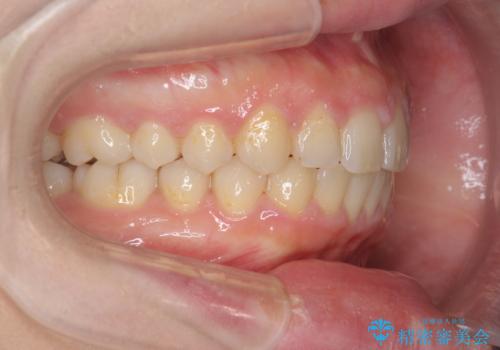

深い噛み合わせ、すきっ歯の改善 ワイヤーを用いたマルチブラケット矯正

- 噛み合わせが深く、前歯が突き出て隙間が出てきたことの改善を希望され矯正治療の相談で当院に初診来院されました。

ワイヤーを用いたマルチブラケット矯正を行うことで深い噛み合わせを改善し、前歯の隙間もなくし審美的な歯列へと治療をおこなっていきます。

深い噛み合わせの改善は前歯の圧下が必要なため、治療期間が長期化することが多いです。